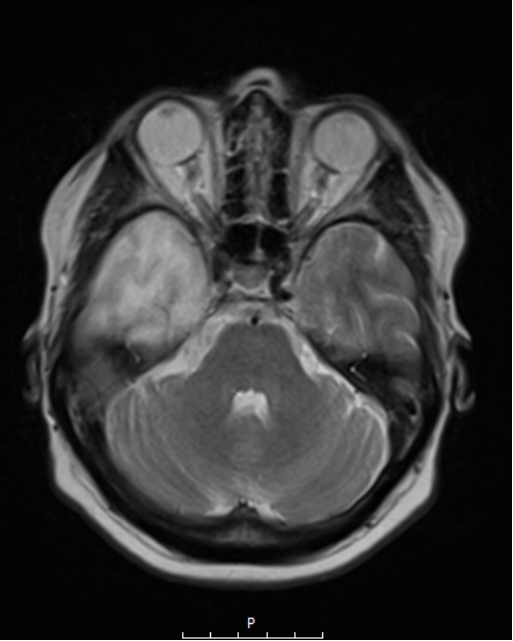

Ο συνδυασμός λοιπόν ενός ασφαλούς χειρουργείου με ταυτόχρονη ολική αφαίρεση του όγκου αποτελεί τον στόχο της σύγχρονης χειρουργικής νευρο-ογκολογίας. Μια υπερολική εξαίρεση στα πλαίσια μιας κροταφικής λοβεκτομής απεικονίζεται στις εικόνες 1 και 2. Αυτό είναι σαφέστατα πιο πιθανό να προσφερθεί από ειδήμονες νευροχειρουργούς (Gousias K, 2024) με ειδική εκπαίδευση σε μεγάλα κέντρα, μεγάλη χειρουργική εμπειρία και εξειδίκευση στην χειρουργική των όγκων καθώς και διεθνή αναγνώριση τους.